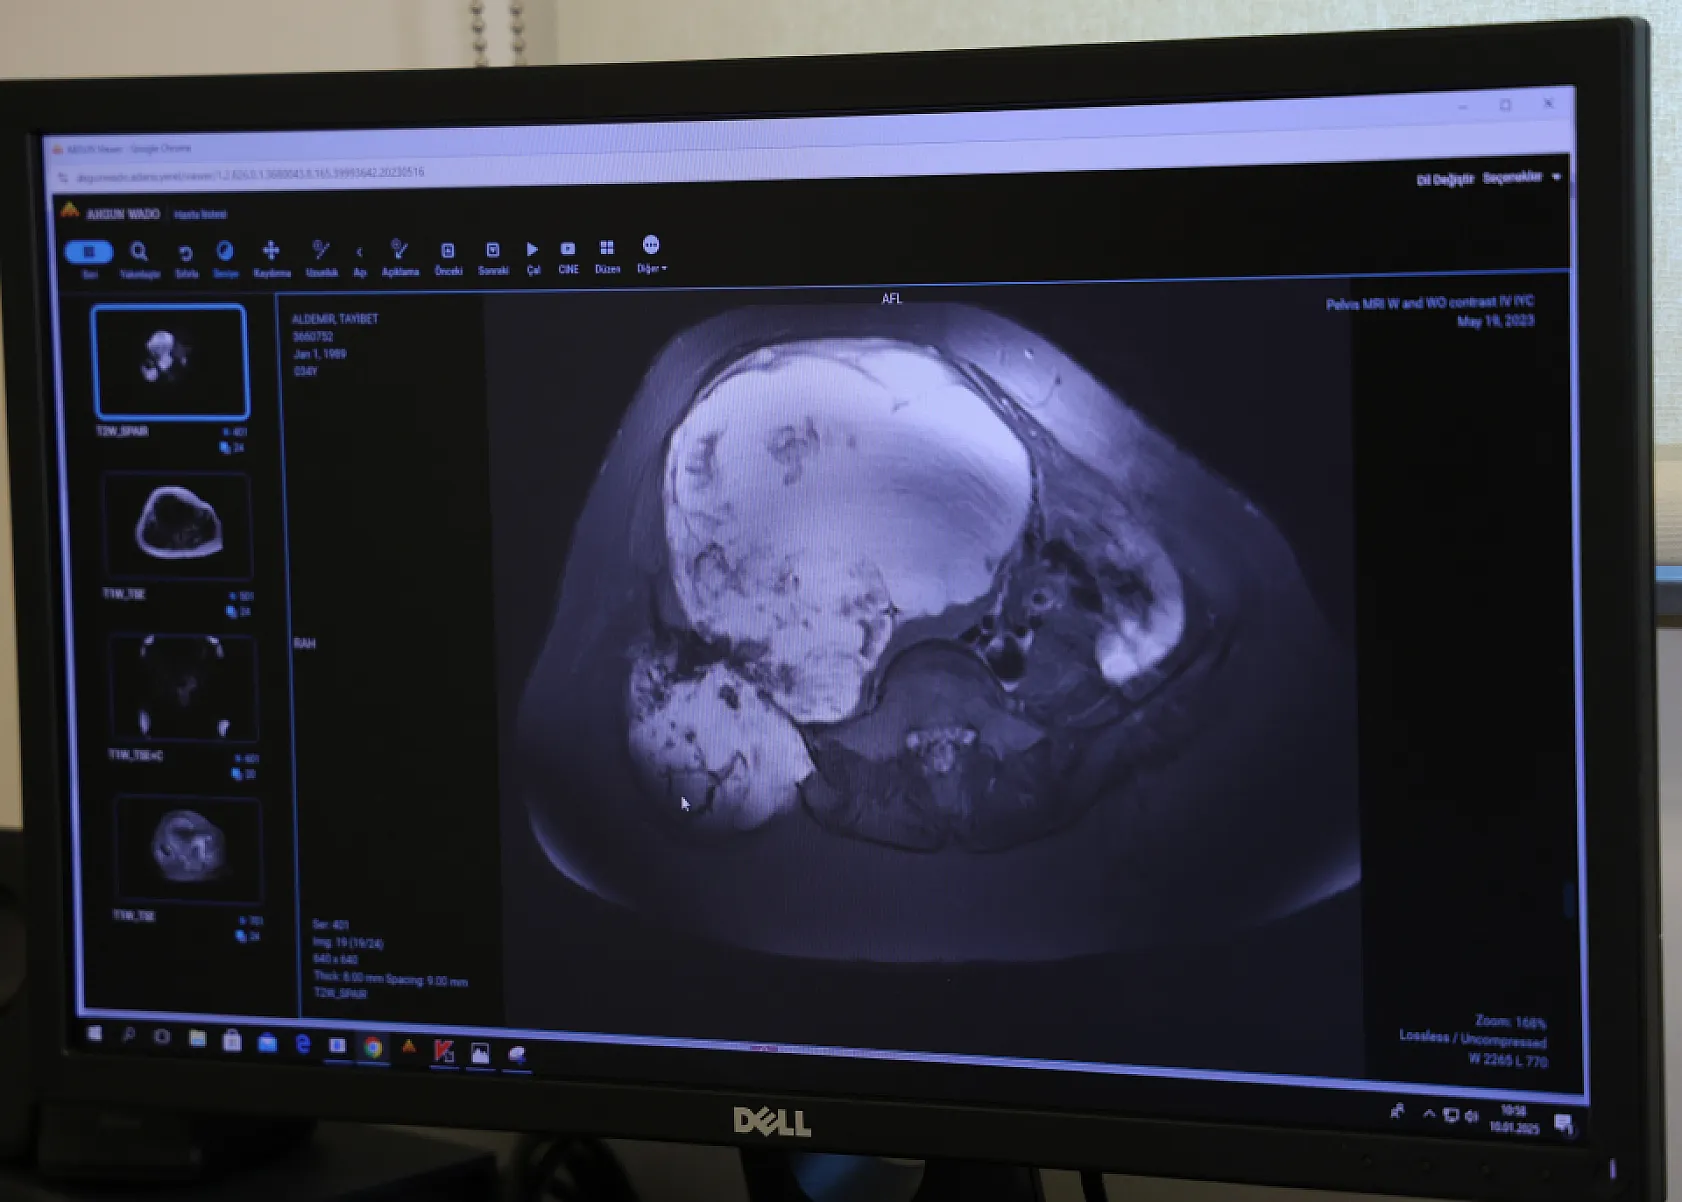

Doğum yaptığı sırada sağ leğen kemiğinde tümör tespit edilen ve doktorların 'Ya bacağın kesilir ya da ölürsün' diyerek ameliyat etmekten çekindiği kadın, Adana'da 6 saat süren 'Pelvik rezeksiyon' ameliyatıyla yeniden sağlığına kavuştu.

İhlas Haber Ajansı'na konuşan Ortopedi ve Travmatoloji Uzmanı Prof. Dr. Ahmet Kapukaya, “Hastamız bize geldiğinde tümörü çok ilerlemişti. Ameliyat olması halinde yüzde 98 bacak kaybı, yüzde 95'de ölüm riski var denilmişti. Ancak Adana Şehir Eğitim ve Araştırma Hastanemizin alt yapısı bu tür ameliyatları yapmaya çok müsait. Bizde hastamıza riskleri anlattık ve ekip halinde bu ameliyatı gerçekleştirdik. Leğen kemiğini bölgeden çıkarttık, tümörü temizledik ve vücuttan alınan diğer kemiklerle o bölgede yeni bir leğen kemiği oluşması için kaynamaya bıraktık” diye konuştu.